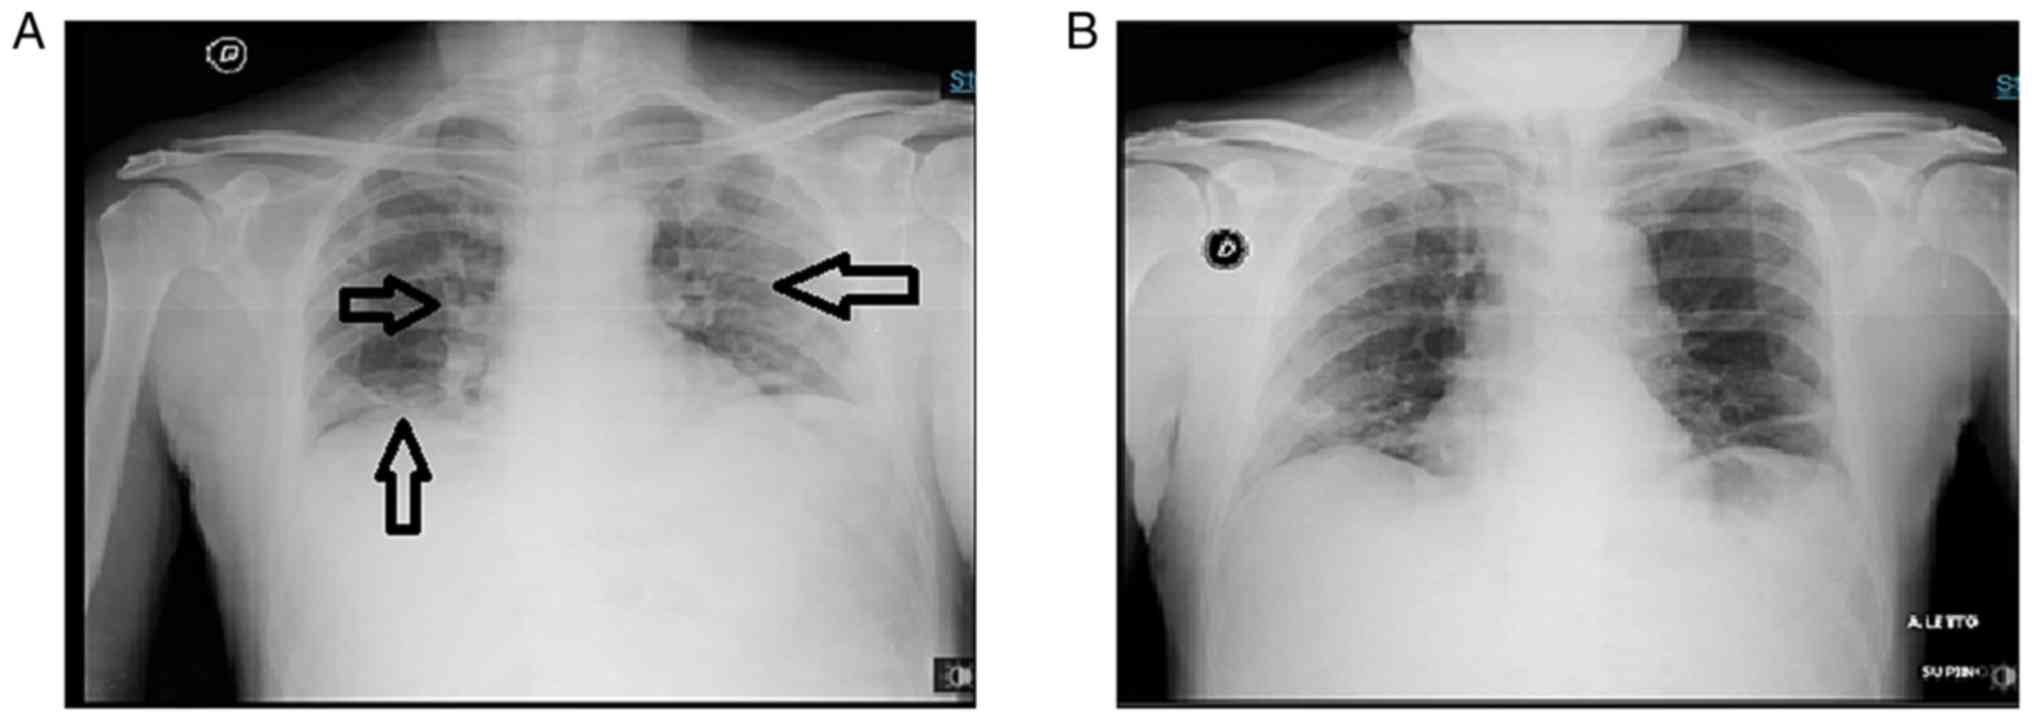

Upon admission, the patient was feverish (temperature, 37.5˚C), with a blood pressure of 110/70 mmHg, a heart rate (HR) of 92 bpm, oxygen saturation rate of 89% in room air and a respiratory rate (RR) of 23/min. Blood tests revealed elevated levels of inflammatory markers along with lymphopenia (Table I). Arterial blood analysis in room air revealed a partial pressure of oxygen (PO2) rate of 60 mmHg, a partial pressure of carbon dioxide (PCO2) rate of 36 mmHg, pH 7.46, and an arterial partial pressure of oxygen (PaO2)/fractional inspired oxygen (FiO2) ratio of 285. A chest X-ray revealed bilateral interstitial pneumonia (Fig. 1).

Within 2 days from tocilizumab administration, the clinical status and respiratory performances of the patient markedly improved. HFNC ventilation was continued for a further 6 days. Subsequently, HFNC treatment was slowly reduced by interchanging it with a Venturi mask for another 2 days, at which time high-flow ventilation was definitively terminated. Both arterial blood analysis and chest X-rays revealed progressive amelioration.